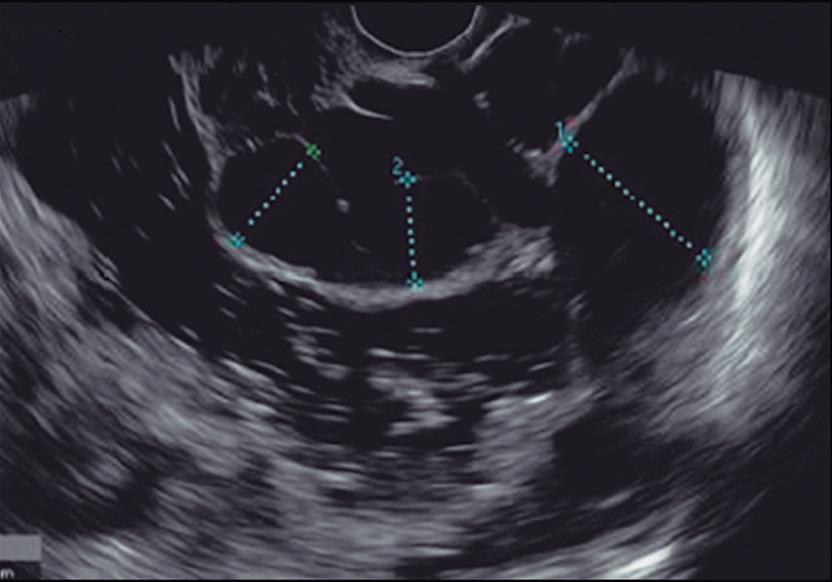

Evaluación endoscópica e histológica

La endoscopía superior es un procedimiento fundamental para el diagnóstico, la evaluación de la respuesta al tratamiento y el monitoreo a largo plazo de la actividad de la EEo. Los hallazgos endoscópicos típicos incluyen edema (reducción de vascularidad), anillos esofágicos fijos, exudados blancos, surcos longitudinales, estenosis, estrechamiento de la luz esofágica, friabilidad de la mucosa (mucosa en papel crepé) y una consistencia firme de la mucosa al realizar biopsias (signo de “tracción" o "resistencia”) en pacientes con fibrosis (Figura 1). Estos hallazgos no son patognomónicos y no constituyen un criterio diagnóstico; sin embargo, cuando se evalúa de forma cuidadosa, en la gran mayoría de los casos se pueden observar.19-21

Un elemento fundamental en la evaluación de la EEo es la aplicación del puntaje de referencia endoscópica para la esofagitis eosinofiílica (EREFS por sus siglas en inglés: Eosinophilic Esophagitis Endoscopic Reference Score).20 El acrónimo EREFS también refleja las cinco características endoscópicas principales de la EEo: Edema, anillos esofágicos (Rings), Exudados, surcos longitudinales (Furrows) y estenosis (Stricture). Estas características se clasifican según su severidad mediante un sistema de puntuación que oscila entre 0 y 9, considerándose la región esofágica con la alteración más marcada. El EREFS cuenta con validación interna y externa, y ha demostrado una elevada capacidad para diferenciar la EEo de otras patologías no relacionadas en poblaciones pediátricas y adultas, además de correlacionarse con la respuesta terapéutica.23-25 Por estos motivos, el EREFS constituye un sistema estandarizado para la evaluación

En el panel A se observa un esófago con edema difuso y pliegues longitudinales; en el panel B se aprecia edema con pliegues y exudados blanquecinos; en el panel C se evidencia un estrechamiento luminal acompañado de anillos esofágicos y exudados; y en el panel D se muestra un desgarro mucoso posterior a la dilatación con bujía de Savary, hallazgo esperado tras este procedimiento terapéutico.

Figura 1. Características endoscópicas de la esofagitis eosinofílica